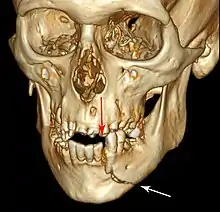

Injuries to supporting bone

This injury involves the alveolar bone and may extend beyond the alveolus.[5][6] There are five different types of alveolar fractures:

- Fracture of the maxilla : Le Fort fracture, zygomatic fracture, orbital blowout

Trauma injuries involving the alveolus can be complicated as it does not happen in isolation, very often presents along with other types of tooth tissue injuries.

Signs of dentoalveolar fracture:

Investigation: Require more than one radiographic view to identify the fracture line.

Treatment: Reposition displaced teeth under local anaesthetic and stabilise the mobile segment with a splint for 4 weeks, suture any soft tissue lacerations.